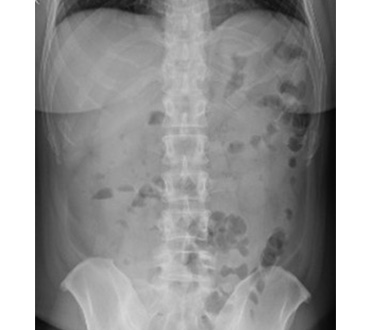

一般撮影室

主にレントゲン写真と呼ばれていてX線を利用し、胸部、腹部、骨などの撮影をします。人体にX線をあて透過したX線をコンピュータで処理し画像にします。迅速に画像を提供できることから、日常の診断に最も多く利用されている検査です。